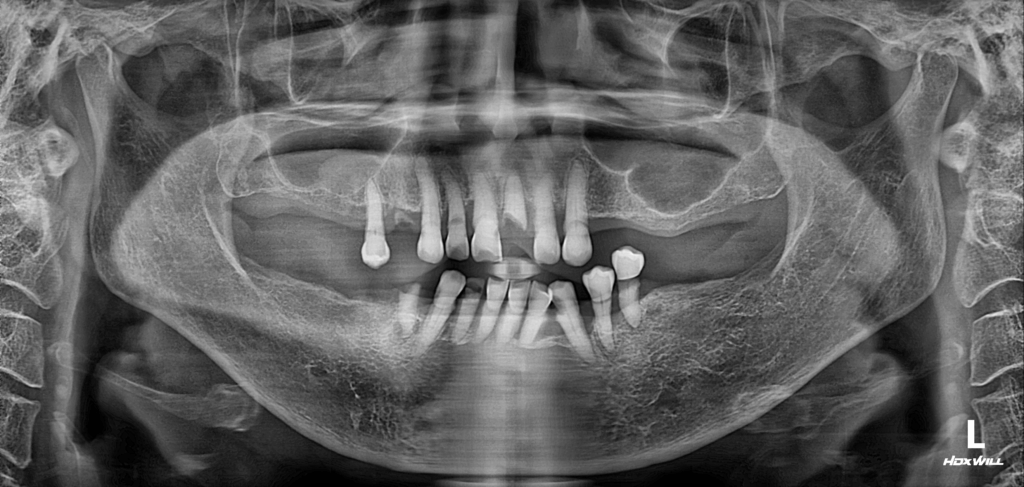

술전 사진

2022.03.28

먼저 하악에서는 하악 전치부와 우측 제2소구치를 발치했습니다. 하악 전치부는 치조골이 상당히 소실되어 치아의 동요도가 크게 증가한 상태였고, 우측 제2소구치는 치근만 남아 있어 기능 회복이 불가능하다고 판단했습니다.

상악의 경우에는 보존 가능한 전치부는 근관치료(신경치료)를 통해 살려냈으며, 치근만 남아 더 이상 보존이 어려운 중절치는 발치를 진행했습니다. 이후, 상악 좌·우측에 필요한 수의 임플란트를 식립하여 전체적인 저작 기능을 안정적으로 회복한 모습을 확인할 수 있었습니다.